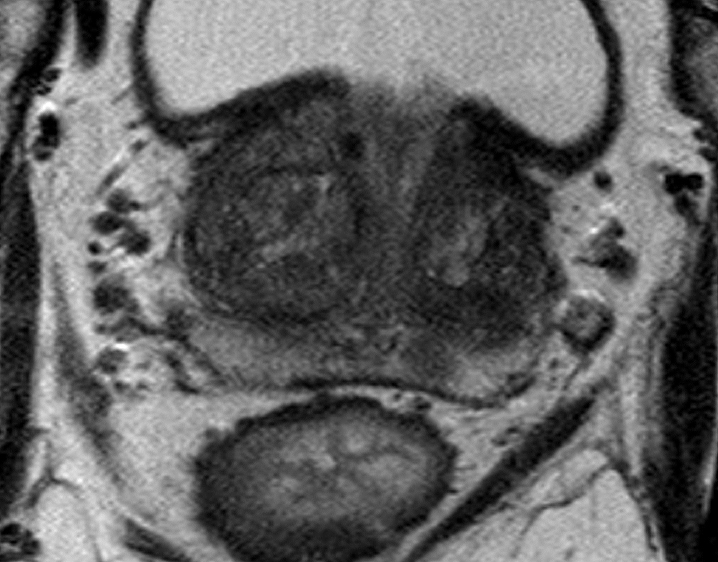

die Diagnostik und Therapie des Prostatakarzinoms hat in den letzten Jahren große Fortschritte gemacht. Dabei nimmt die multiparametrischen Magnetresonanztomographie (mp-MRT) der Prostata eine zunehmend wichtigere Stellung in der individuellen Therapie-Entscheidung ein.

Anlässlich der inzwischen breiten Einführung dieser radiologischen Untersuchungstechnik in urologische Richtlinien und den klinischen Alltag möchten wir Sie herzlich zu unserer Fortbildungsveranstaltung über die mp-MRT der Prostata einladen. Diese Fortbildung ist interdisziplinär ausgelegt und richtet sich trotz des primär radiologischen Themas neben Radiologen auch ausdrücklich an Urologen und andere urologisch interessierte Kollegen.